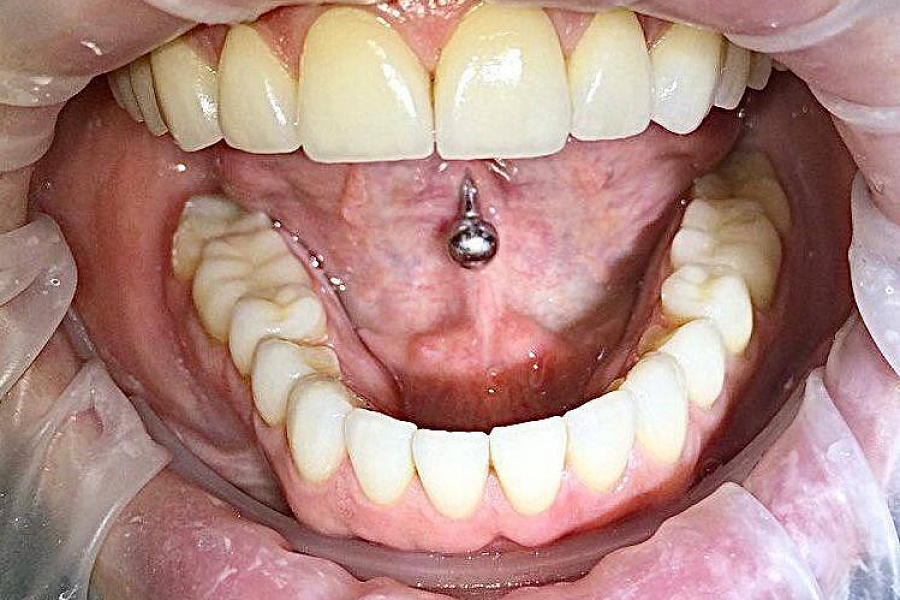

- выраженная стираемость зубов

- поврежден край переднего зуба семечками

В первую очередь был запрос на эстетическую часть. Пациентка хотела, чтобы новые зубы выглядели естественно.

Провели санацию, сделали и установили красивые натуральные виниры.

Результат на фото говорит лучше всяких слов. Пациентка очень довольна результатом!